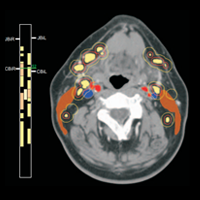

MEDICAL DIAGNOSIS

Magical Lens